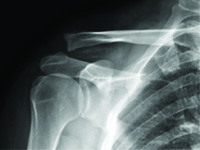

GinekologiaZwichnięcie stawu barkowo-obojczykowego odnosi się do całkowitej lub częściowej niewspółosiowości powierzchni stawowych sąsiadujących ze sobą łopatki i obojczyka [1]. Jest to uraz, który często występuje w sportach kontaktowych, takich jak piłka nożna, judo, rugby i wiele innych. Jest to również stosunkowo częsty uraz w codziennych czynnościach, w wyniku upadku podczas spaceru lub upadku z krzesła z uderzeniem w obręcz barkową [2], [3].<br />W zależności od stopnia urazu, zalecane podejścia różnią się od leczenia zachowawczego (stopień I i II) do leczenia chirurgicznego (powyżej stopnia III).<br />Zalecenia dotyczące leczenia zachowawczego to: chłodzenie, leki przeciwbólowe i uniesienie kończyny. Leczenie chirurgiczne polega na chirurgicznej stabilizacji zwichnięcia. Istnieje wiele technik i metod unieruchomienia urazu, w tym: druty Kirschnera, przy użyciu TightRope, podwójny Endobutton, MINAR, Copeland i Kessel, Waver i Dunn czy dedykowane płytki [3], [4].<br />.